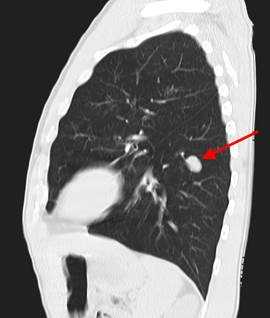

У пациента был выявлен раковый узел в 6 сегменте нижней доли слева. После резекции путем гистологического исследования верифицирован плоскоклеточный рак легкого. Томография в данном случае не дала типичную картину злокачественного новообразования.

2) Плоскоклеточный неороговевающий рак - часто встречающийся вариант - до 35% всех случаев образований легких. Характеризуется наилучшим прогнозом, редко метастазирует. Примерно в 65% развивается в одном из центральных бронхов и обуславливает картину ателектаза на КТ и рентгеновских снимках, в 35% развивается в периферических бронхах и выглядит как солидный единичный узел, часто с полостью распада в центре, похожий на абсцесс.

Типичный периферический рак легкого (аденокарцинома) на МСКТ. Справа в 6 сегменте легкого выявлен плотный мягкотканный узел со спикулами, деформирующий и подтягивающий к себе междолевую плевру.